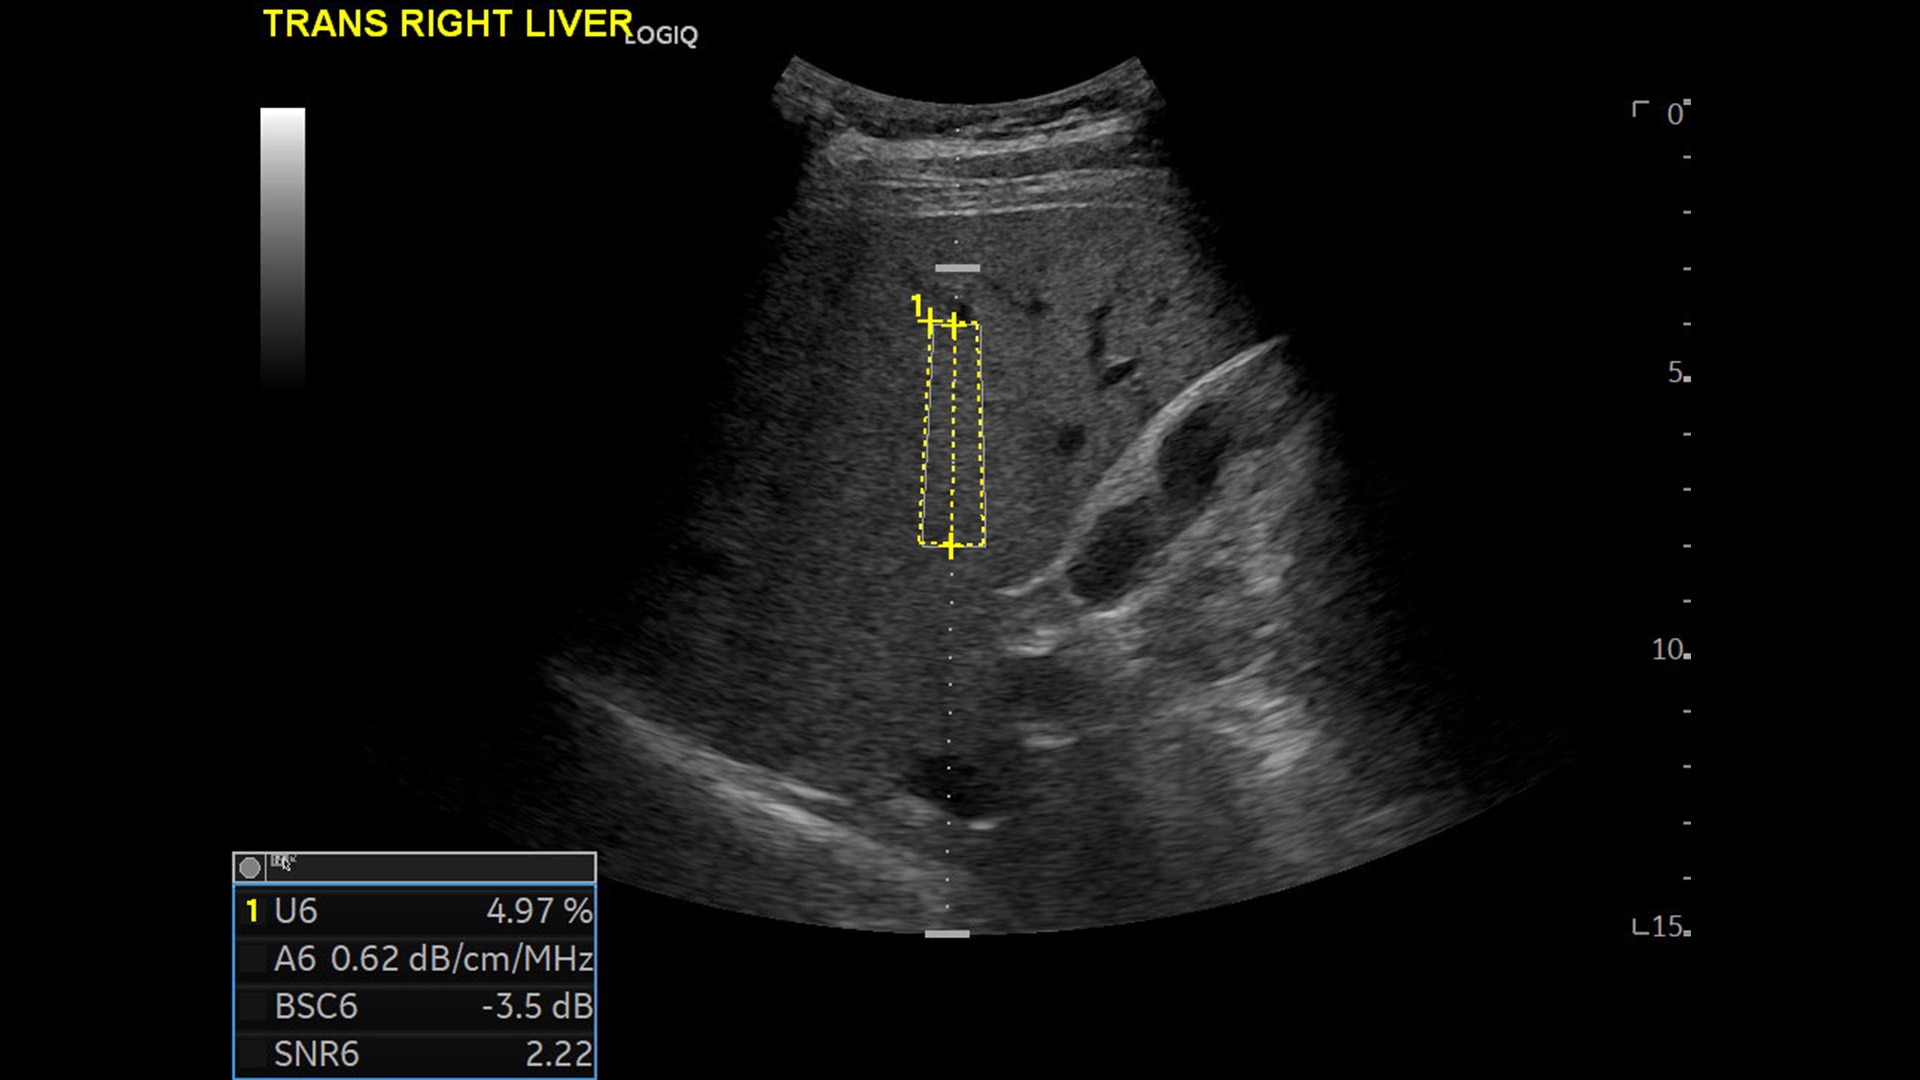

Strength and power to enhance clinical capabilities and deliver exceptional image quality